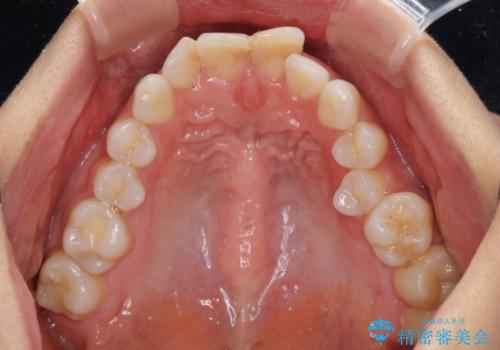

- 口元の閉じにくさと、奥歯の咬み合わせを気にして来院された患者様です。

左下の大臼歯2本が顕著に舌側に傾斜しているため、まずは奥歯の咬み合わせを改善をし、その後上下左右の第1小臼歯4本を抜歯することで口元を引っ込めながら整えることとしました。

奥歯の咬み合わせ改善には1年ほどの期間と処置中の噛みにくさを強いることとなりましたが、抜歯後はスムーズに治療を完了させることができました。

歯ぎしりの際に奥歯が干渉していた咬み合わせも理想的な状態に改善できました。